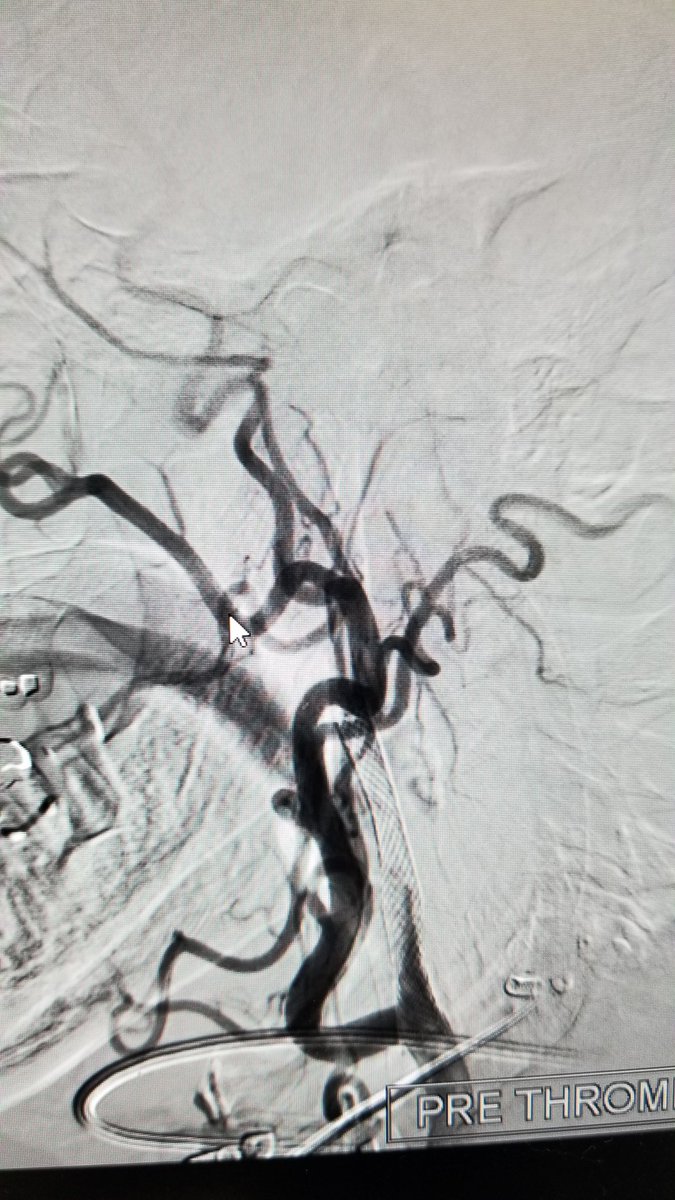

@Aggour

Mohamed Aggour

5 years

Stenting the occluded carotid stent The 24/7 #stroke service @RoyalLondonHosp Stroke team in action! @RLHINR @NHSBartsHealth @BSIR_News @UKNGNeuro @hldmak @drpaulbhogal

0

2

1